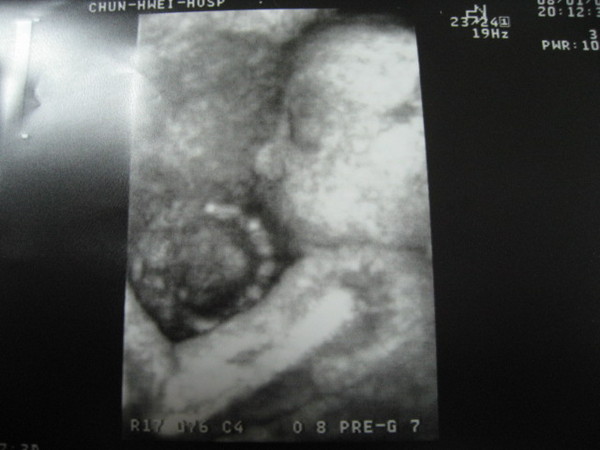

恩...今次附上鋀鋀3D超音波翻拍照...

看看傳說中的木乃伊超音波相片..和終於被承認像我的圓鼻子...哇哈哈![]()

p.s.手中抱著的那一團,聽說是臍帶..